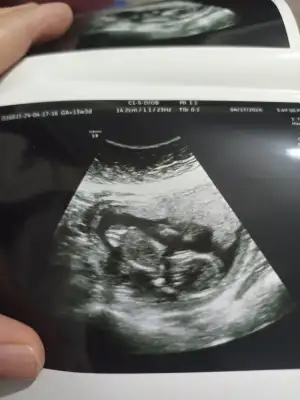

Bizde 13 haftalık olduk bana da tahminde bulunabilir misiniz çok merak ediyorum 💕💕

Merhabalar benimkini de yorumlayabilir misiniz acaba 🤗🤗 10+1 haftalık burda. Ama 6-7 gün fazla büyümüş yani 11+1 gibi 🤗🥰

Rica etsem bana da bakar mısınız? Bu resimde 10+1.Kalp atımı 8. Haftada 150 civarıydı en son gittiğimde sormadım şimdiden teşekkürler🫶🏻